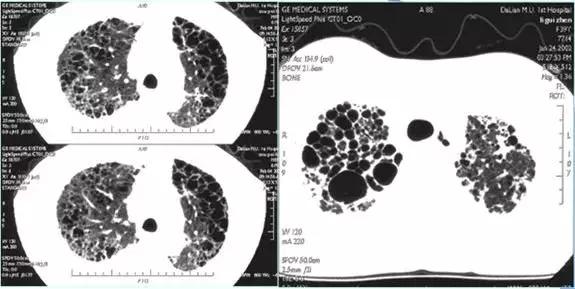

两肺弥漫蜂窝影-肺淋巴管肌瘤病,均为女性